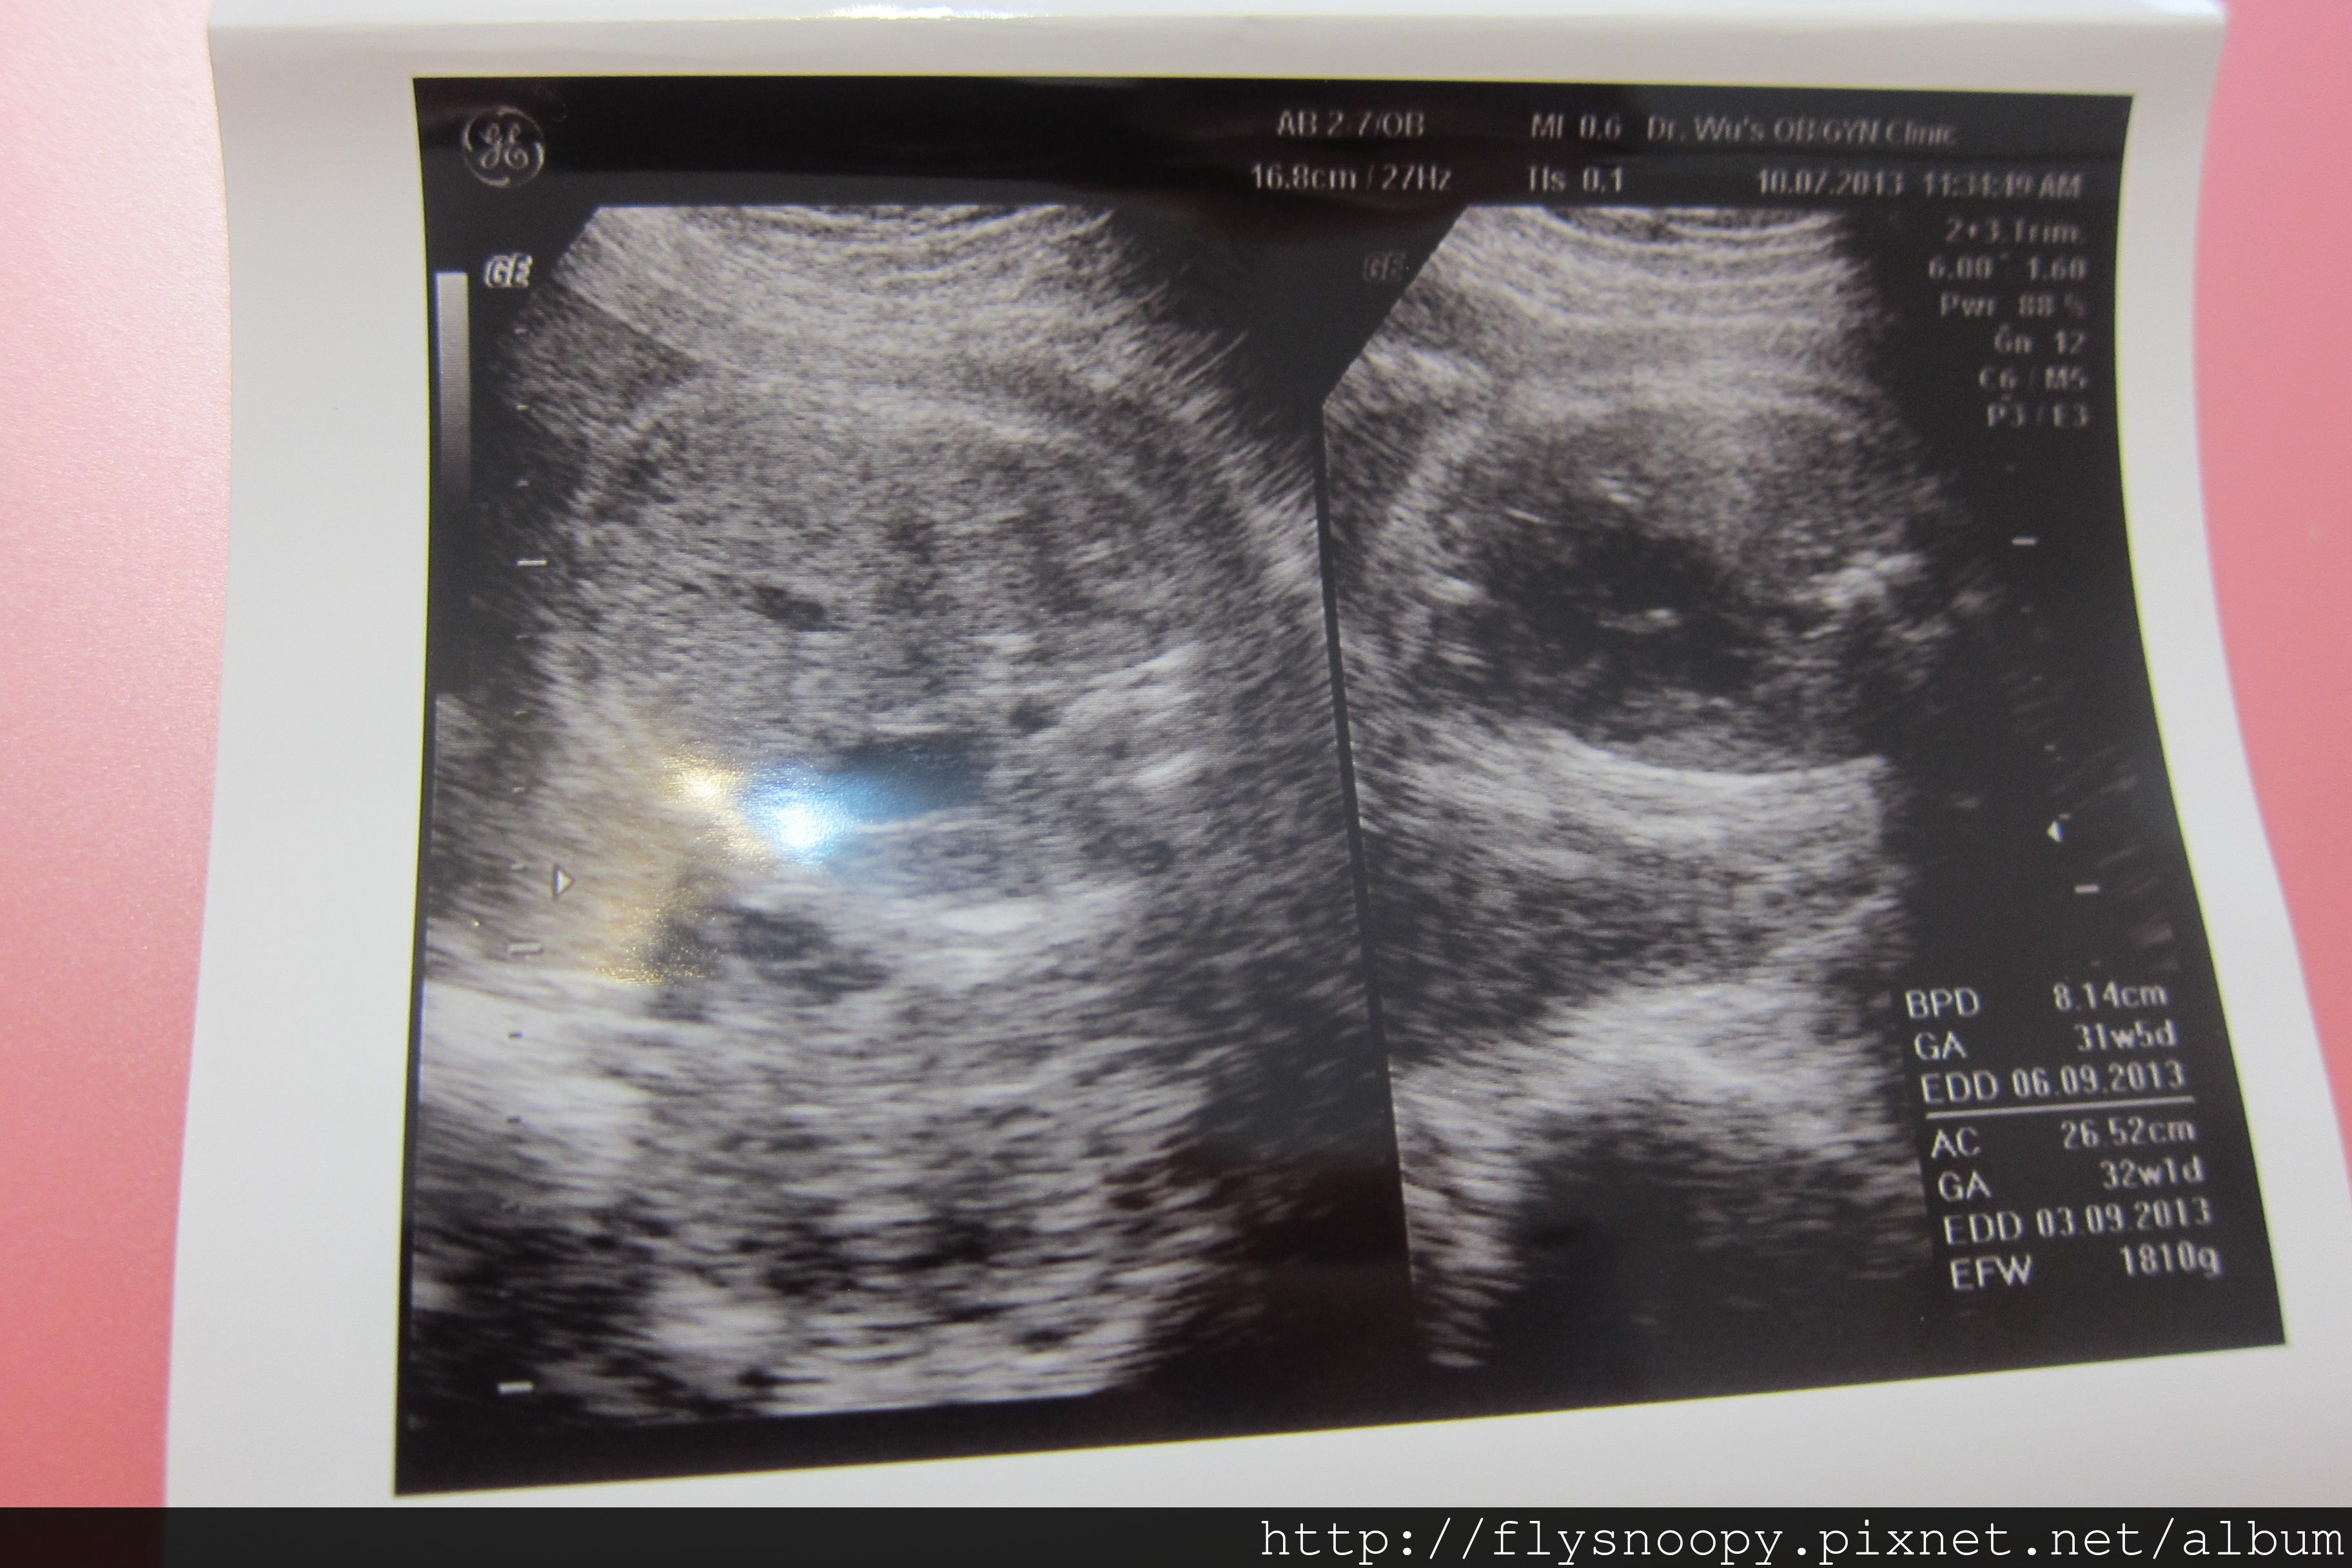

7/24 第8次產檢

這次一樣是早上去醫院,因為晚上人實在是好多,都要等很久

第八次產檢記錄

體重:63.5

血壓:105/67

尿糖、尿蛋白:正常

EFW:2003(突破2000囉~~~~~)